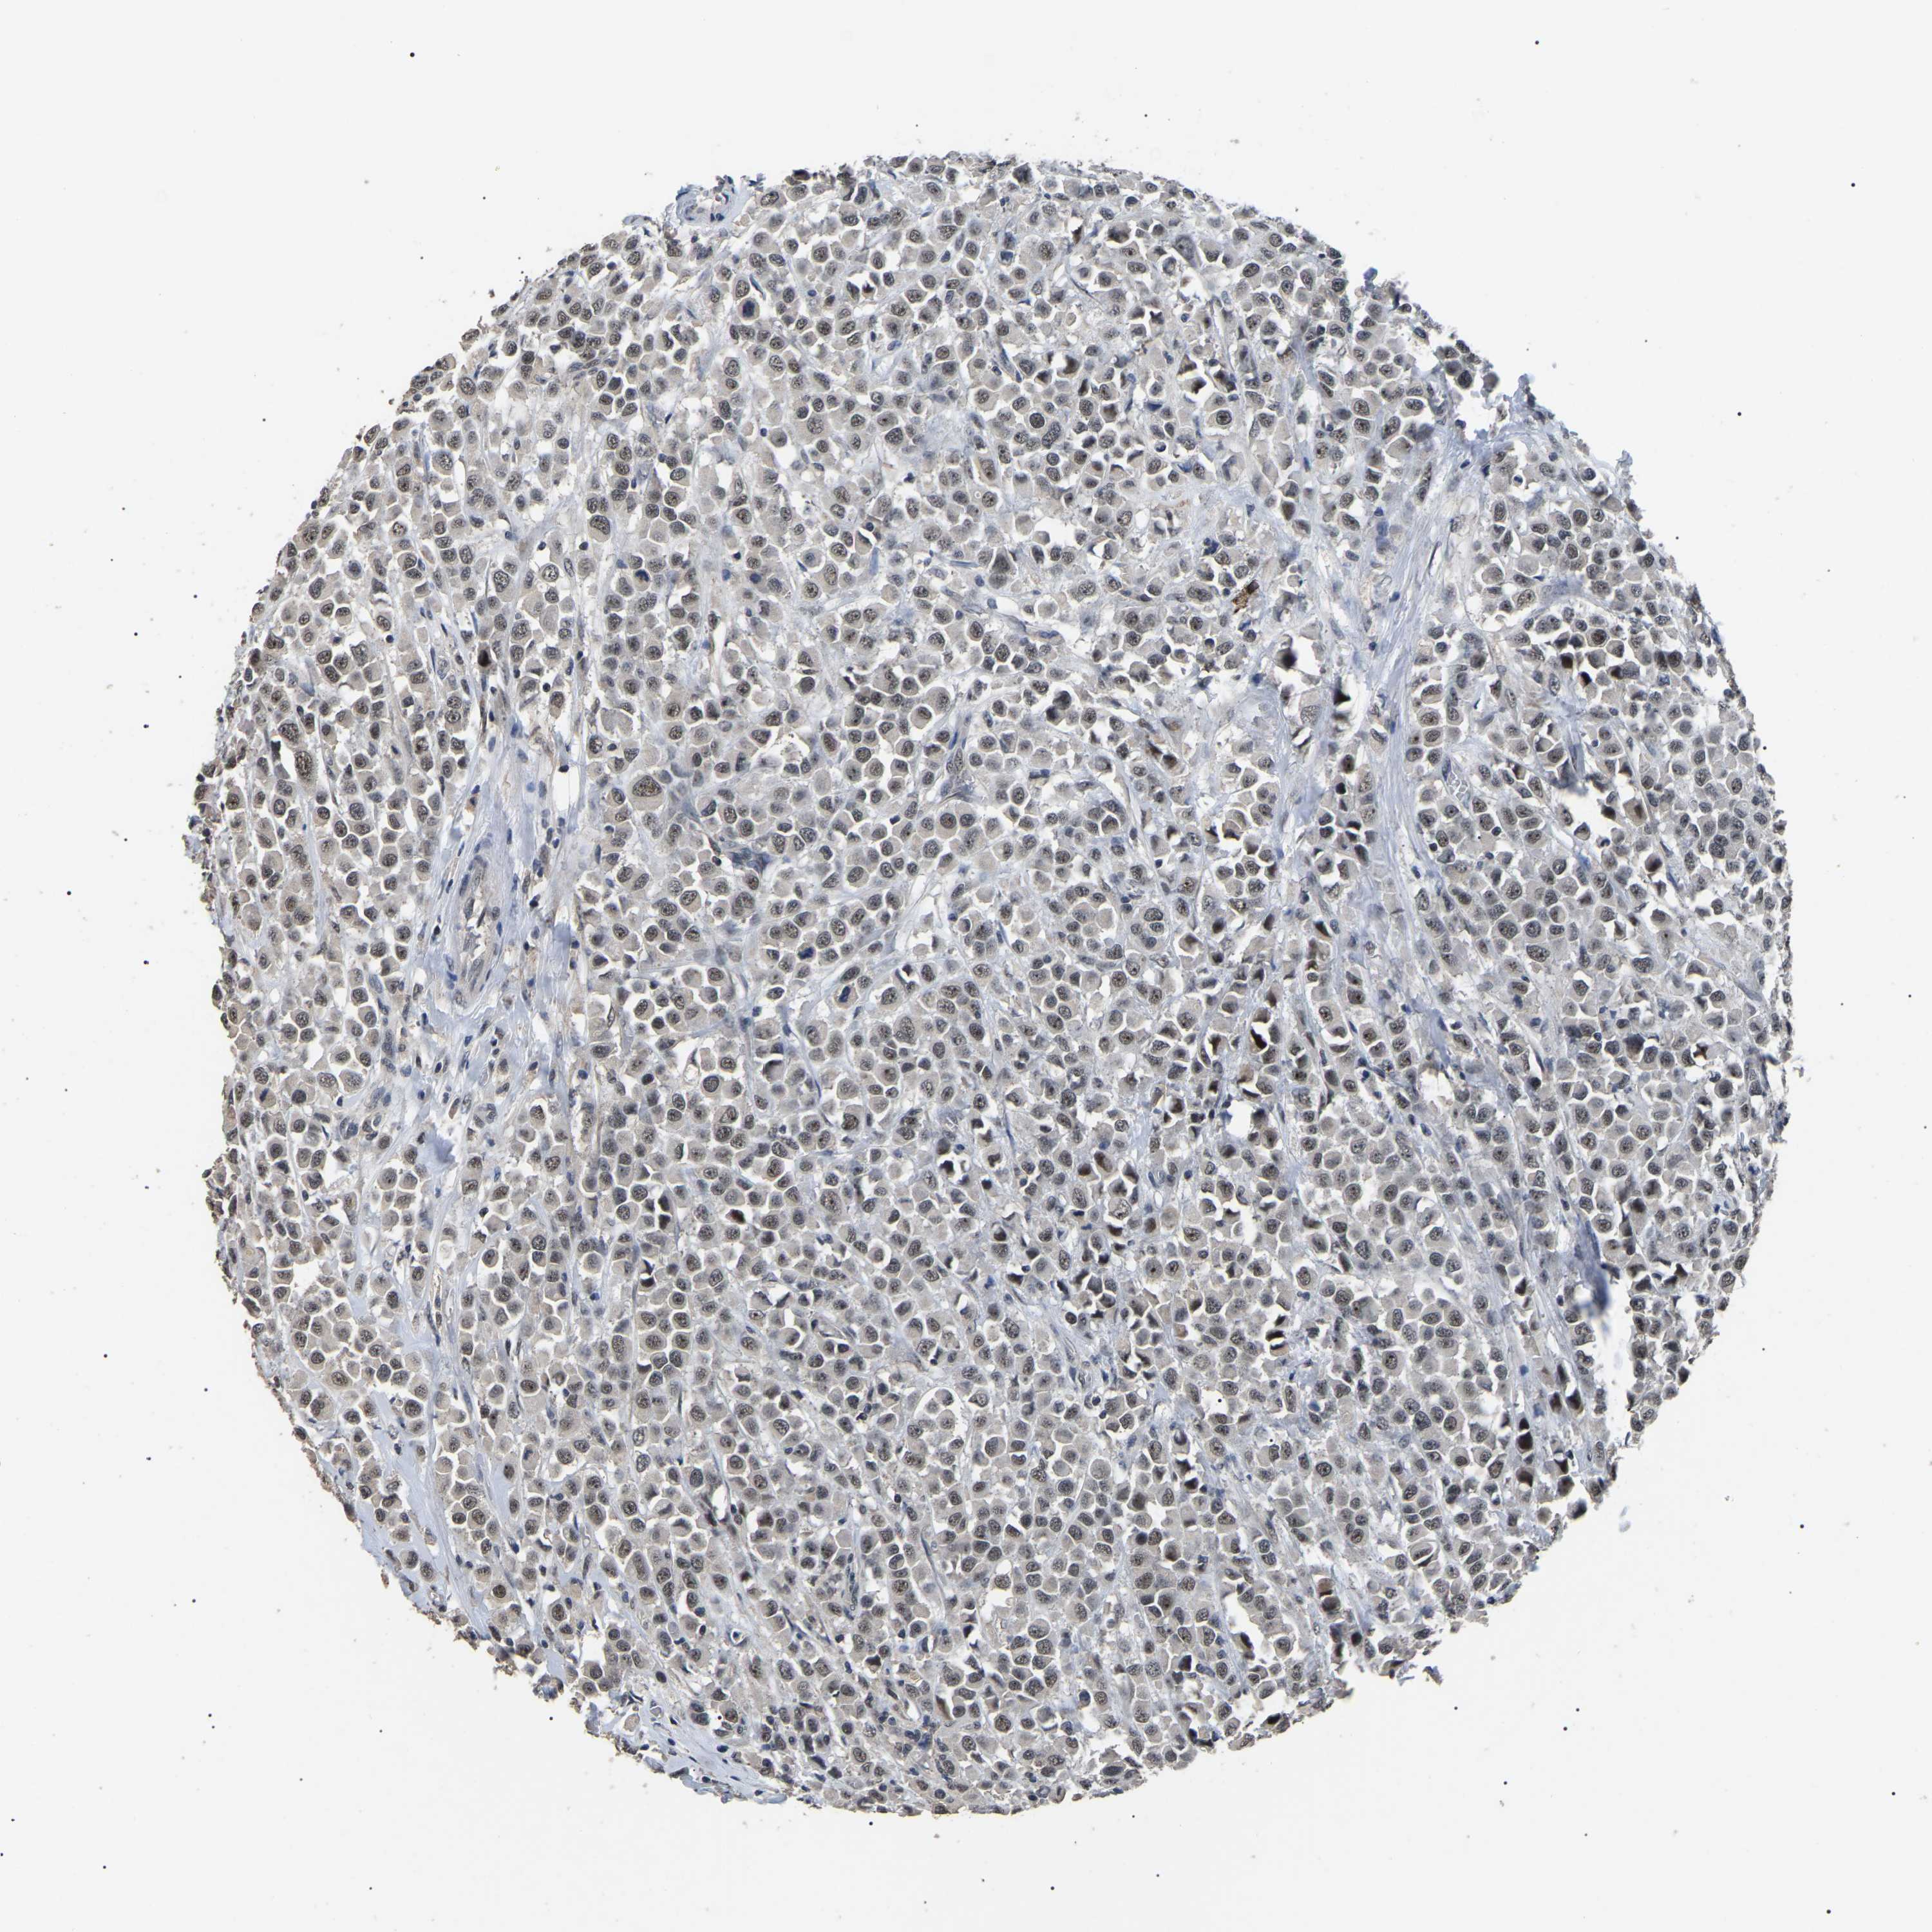

CANCER BREAST CANCER Show tissue menu

BRCA TCGA BRCA VALIDATION PROTEIN EXPRESSION